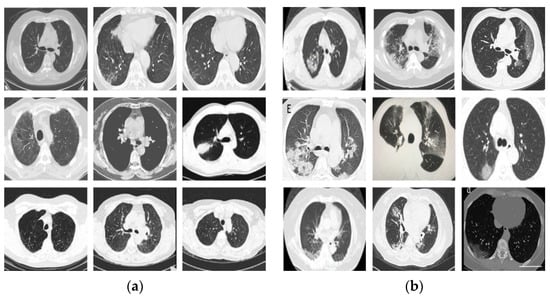

3.1. Dataset and Experimental Setup